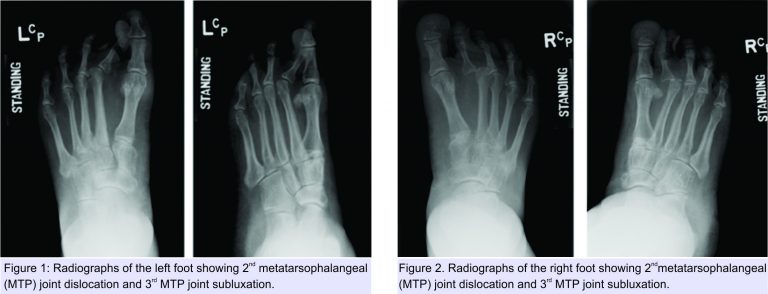

A 50-year-old female patient was referred to the foot and ankle clinic with the existing diagnosis of HCS. She complained of bilateral foot pain and deformities of the toes. Physical examination revealed left-sided dislocation of the second metatarsophalangeal (MTP) joint, subluxation of the third MTP joint, and Morton’s neuroma between the third and fourth toes (Fig. 1). Examination of the right foot similarly demonstrated second MTP joint dislocation and third MTP joint subluxation, along with second-third and third-fourth intermetatarsal Morton’s neuromas (Fig. 2).